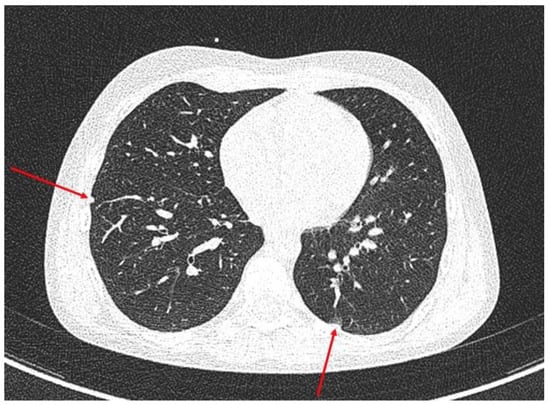

| Diagnosis | Right lung: 5 nodules (5 × 5 mm) Left lung: 2 nodules (4 × 5 mm) Left hilus: 2 lymph nodes (max size 16 mm). | CT and MRI: a tumour in the right kidney (81 × 81 × 104 mm), renal vein infiltration, tumour capsule rupture, right hepatic lobe infiltration, suspected metastases to the right adrenal gland and the peritoneum. ileocecal lymph node (15 × 5 mm) | confirmed active disease process in the same places as in CT/MRI |

| Follow up after kidney tumor resection and 2 cycles sunitinib 15 mg/m2 | unchanged size of previously described pulmonary lesions, but Right lung: a new single nodular lesion (10th segment) Right hilus: new 2 lymph nodes (10 × 10 and 20 × 11 mm) | Ileocecal lymph node PR (12 × 5 mm) | confirmed active disease process in the same places as in CT/MRI |

| Follow up after 8 cycles sunitinib 25 mg/m2 | Right lung: 3 nodules (3 × 4 mm) Left lung: 2 nodules (3 × 3 mm) Left hilus: 2 lymph nodes max size 10 mm Right hilus: 2 lymph nodes (10 × 5 and 15 × 11 mm) | Ileocecal lymph node SD (13 × 5 mm) | |

| Follow up after 13 cycles sunitinib 25 mg/m2 | Right lung: PD 3 nodules (max size 9 mm) Left lung: PD 2 nodules (max size 4 × 6 mm) Left hilus: SD Right hilus: SD | Ileocecal lymph node PD (12 × 19 mm) | |

| Follow up after 4 cycles of nivolumab 3 mg/kg mth | Right lung: PR 3 nodules (max size 5 mm) Left lung: PR 2 nodules (max 3 mm) | Ileocecal lymph nodes SD (13 × 19 mm) | Partial metabolic regression |

| Follow up after 18 cycles nivolumab 3 mg/kg mth | Right lung: PR 3 nodules (max 3 mm) Left lung SD Left, right hilus lymph nodes: SD | CR | Complete metabolic regression all showed places |